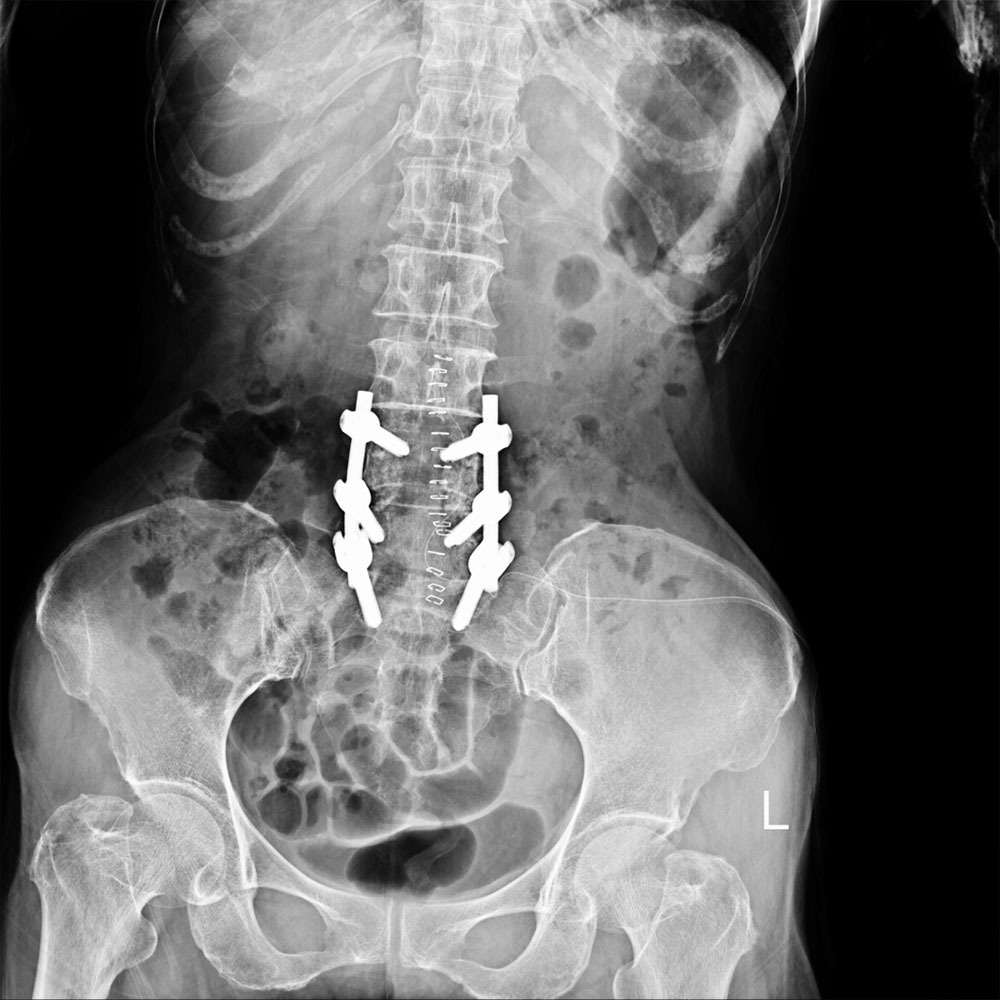

The type of pain that one can experience with Post Laminectomy Syndrome could be dull or achy back pain, pain that radiates to the hips, buttocks or thighs, or sharp pain in the back and legs. Treatments for this syndrome can range from medication and physical therapy, and even additional surgery if the pain is too great. It is crucial to seek a pain management doctor in New York because an accurate diagnosis is imperative. A precise diagnosis is necessary to facilitate an effective plan of treatment. An evaluation may include x-rays, MRIs, EMGs, and other means of identification. After identifying the source of your ailment, a treatment plan can be prescribed and implemented.